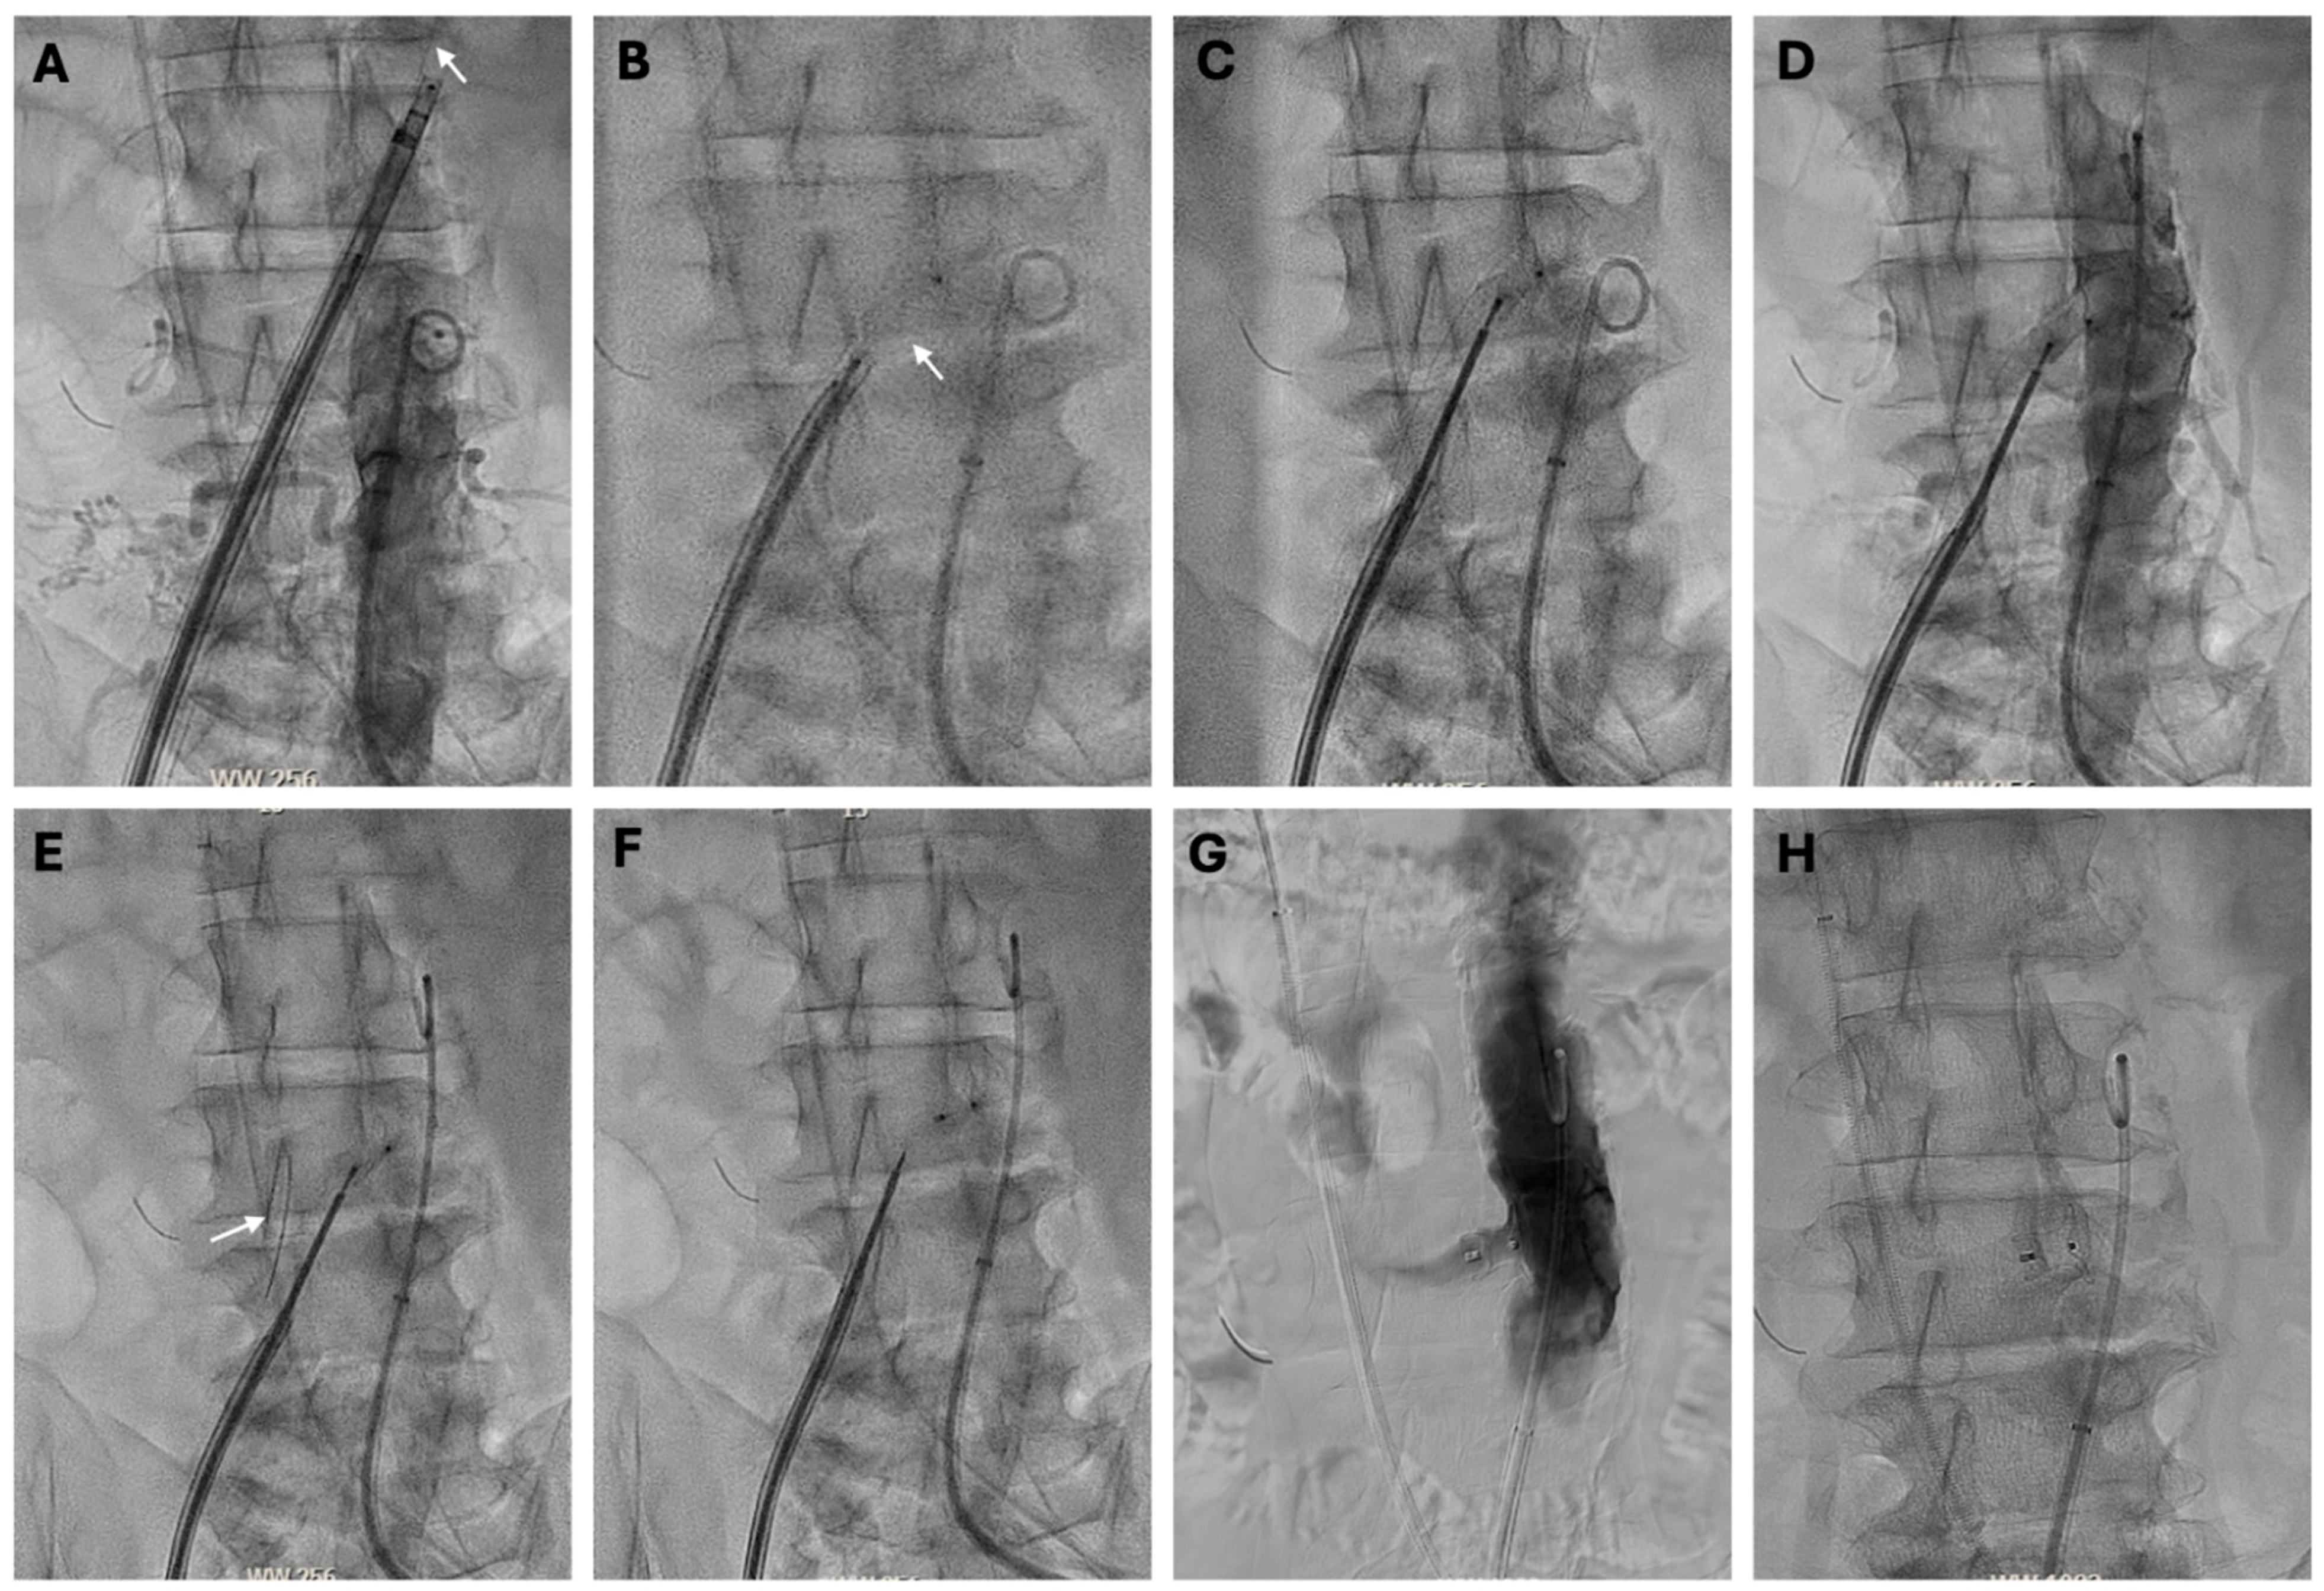

4.5.3. Transcaval Access Technique

4.5.4. Closure

- Lederman, R.J.; Babaliaros, V.C.; Greenbaum, A.B. How to Perform Transcaval Access and Closure for Transcatheter Aortic Valve Implantation. Catheter. Cardiovasc. Interv. 2015, 86, 1242–1254. [Google Scholar] [CrossRef] [PubMed]